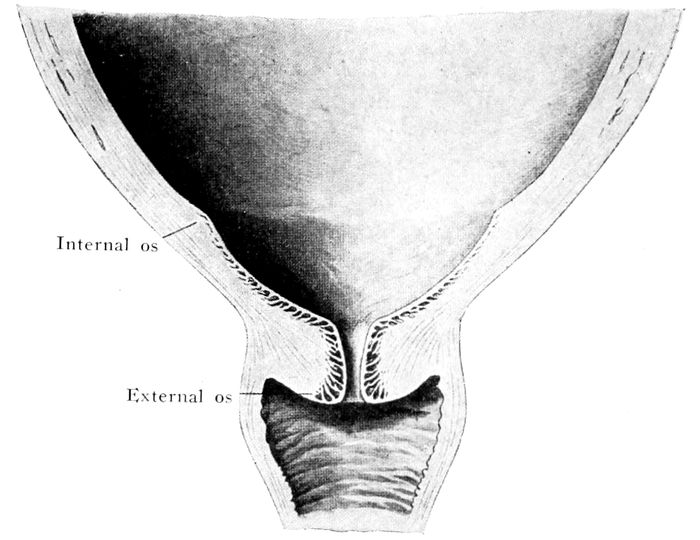

The bag of waters begins to act on the cervix |

111 |

| |

| 36. |

The effect of the pains. The cervix before labor begins |

112 |

| |

| 37. |

The effect of the pains. The cervix begins to be “effaced” |

112 |

| |

| 38. |

The effect of the pains. The cervix is effaced, and the dilatation of the os begins |

113 |

| |

| 39. |

The effect of the pains. The cervix is effaced and the os continues to dilate |

113 |

| |

| 40. |

The cervix is effaced and the os dilated |

115 |